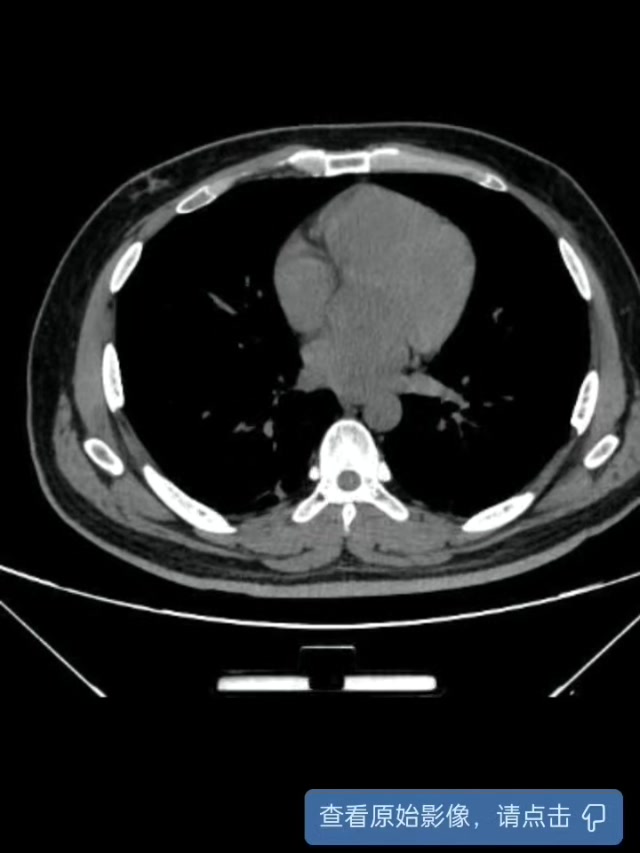

穿刺后次日复查CT:

穿刺引流后,患者未再发热,病情控制。继续抗感染治疗,等待二期手术处理结石。